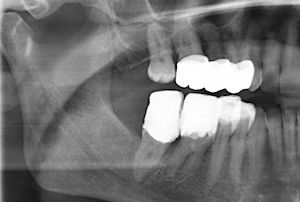

Beachte: Die Fraktur verläuft mesial 2 mm weit durch eine initiale Karies, zentral 6 mm neben einer Amalgamfüllung, und distal 3 mm lang mitten durch eine intakte Kompositfüllung. Diese ist mittig gespalten, aber nirgends vom Zahn abgerissen. Das Zentrum der Amalgamfüllung ist nicht gespalten.

Der Patient ist ein Heavy biter und kam seit Jahren immer wieder mal um Hyperbalancen einzuschleifen. Zudem war dieser +6 der letzte Molar links oben.

Auch auf diesem Röntgenbild ist weder die Hyperbalance noch der kleine Höckerwinkel mit der vertieften Zentrik sichtbar. Die initiale Karies war klinisch nicht sichtbar.